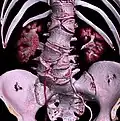

Congenital block vertebra of the lumbar spine. CT volume rendering. -

Congenital block vertebra of the lumbar spine. CT volume rendering.